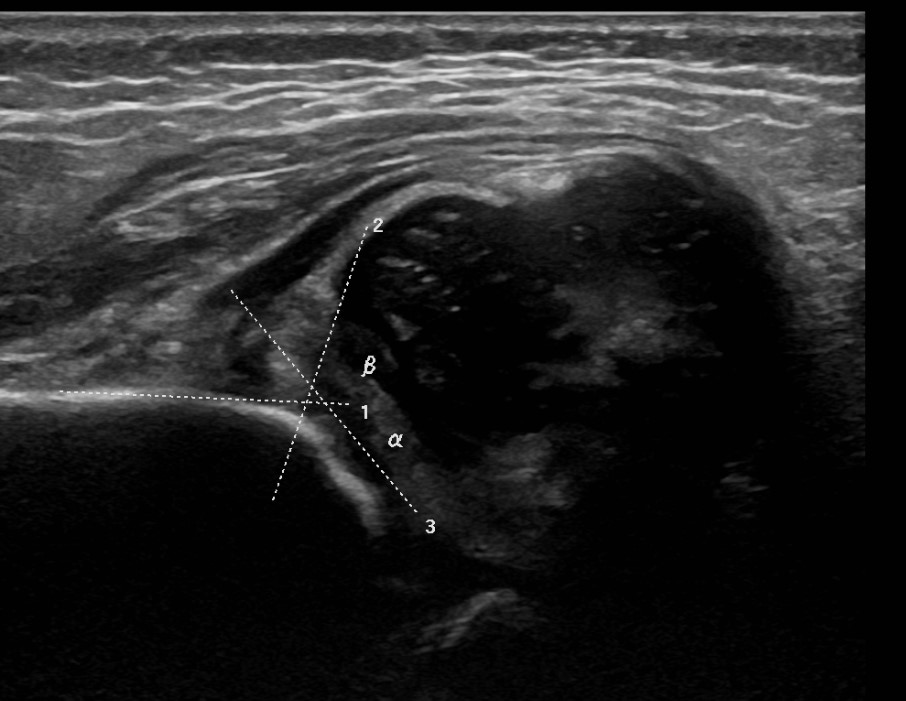

| Alpha Angle | Beta Angle | Dynamic |

|---|---|---|

|

Between ilium & bony roof acetabulum

Between ilium & cartilage roof / labrum

Ultrasound Ortolani / Barlow

Normal > 60°

The lower the alpha angle, the more subluxed the hip is

Normal < 60o |

Alpha angle between ilium and bony roof of acetabulum

Beta angle between ilium and cartilage roof / labrum